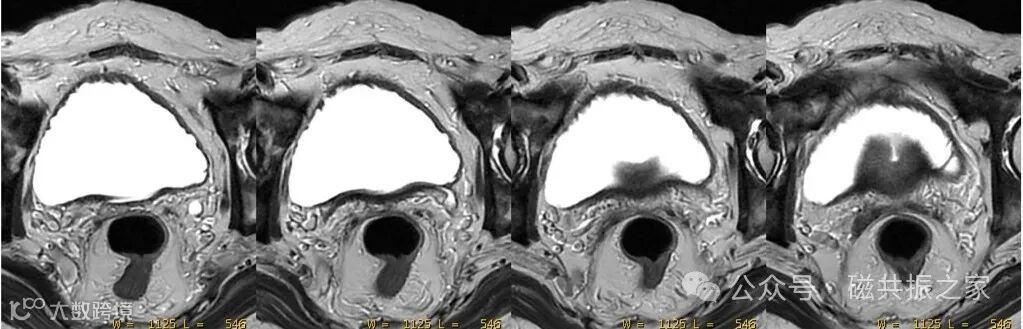

宽带宽+长回波链可使脂肪更亮,获得更优异的组织对比图像。如在盆底脏器的扫描中常使用该方式来突出对比。

在对有复杂运动部位的扫描中,难以通过补偿技术(或未使用补偿技术)改善其运动伪影时,建议使用较宽的带宽扫描。如对于腹、盆脏器的蠕动时。